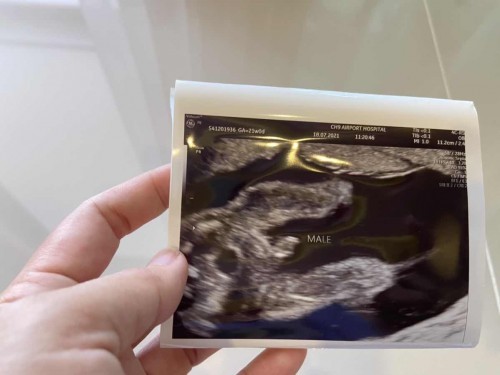

อัลตร้าซาวด์ อายุครรภ์ 5 เดือน

วันนี้คุณแม่ลืมนัด รพ ต้องโทรตาม วันนี้ต้องซาวด์แบบละเอียด ดูความสมบูรณ์ของร่างกายตัวน้อยในครรภ์ คุณหมอบอก อยู่ในเกณฑ์ที่ดีครับ หัวใจ ปอด น้ำคร่ำ ปกติ ปากแหว่ง เพดาน โหว่งไม่มี ช่วงที่คุณหมอซาวด์แม่ภาวนาตลอดให้เจ้าหนูสมบูรณ์แข็งแรง💓 ลูกชายแม่ชอบโชว์จุ๊ดจู๋ตลอดเลย 👶🏻 #ท้องแรกคะ #ใครมีประสบการณ์